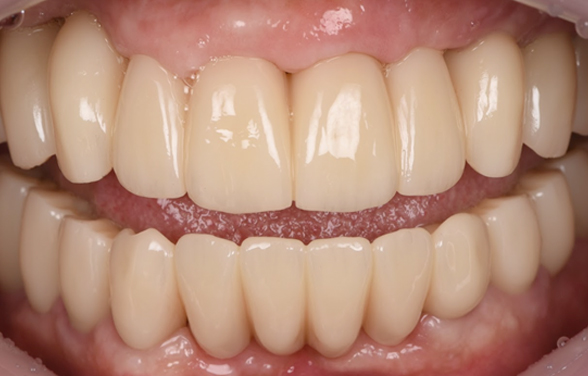

최종 치아 위치 먼저 결정 -> 식립

먼저 뼈 있는 곳 식립 -> 최종 치아 올림